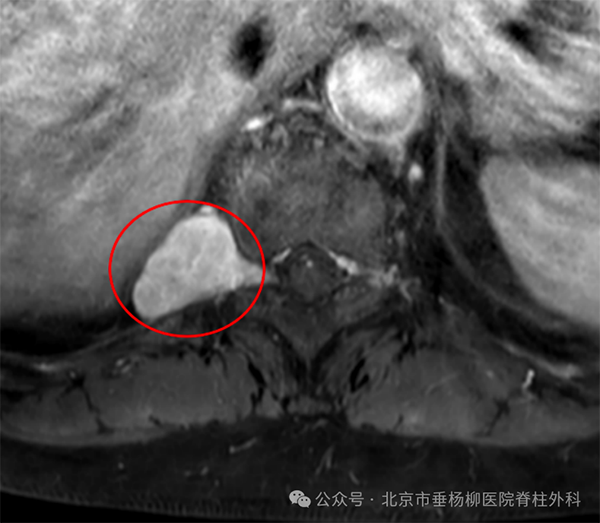

▲T2加权像平扫发现T10/11水平右椎间孔及外侧神经根走行区域

一2*3cm的类圆形占位,边界清晰。

▲T2加权像增强扫描可见明显强化

根据影像学表现,初步考虑神经鞘瘤可能性大。体格检查肢体感觉、肌力、反射未见明显异常。随即骨四科(脊柱外科)的医生对手术风险进行了评估,由于生长在这个位置的神经鞘瘤由于其所处位置紧邻多个重要解剖结构,手术过程中发生胸膜、肋间神经、肋间动/静脉乃至脊髓损伤的风险较大。与患者及家属详细交代手术风险,患者及家属十分信任我们并积极要求手术治疗。